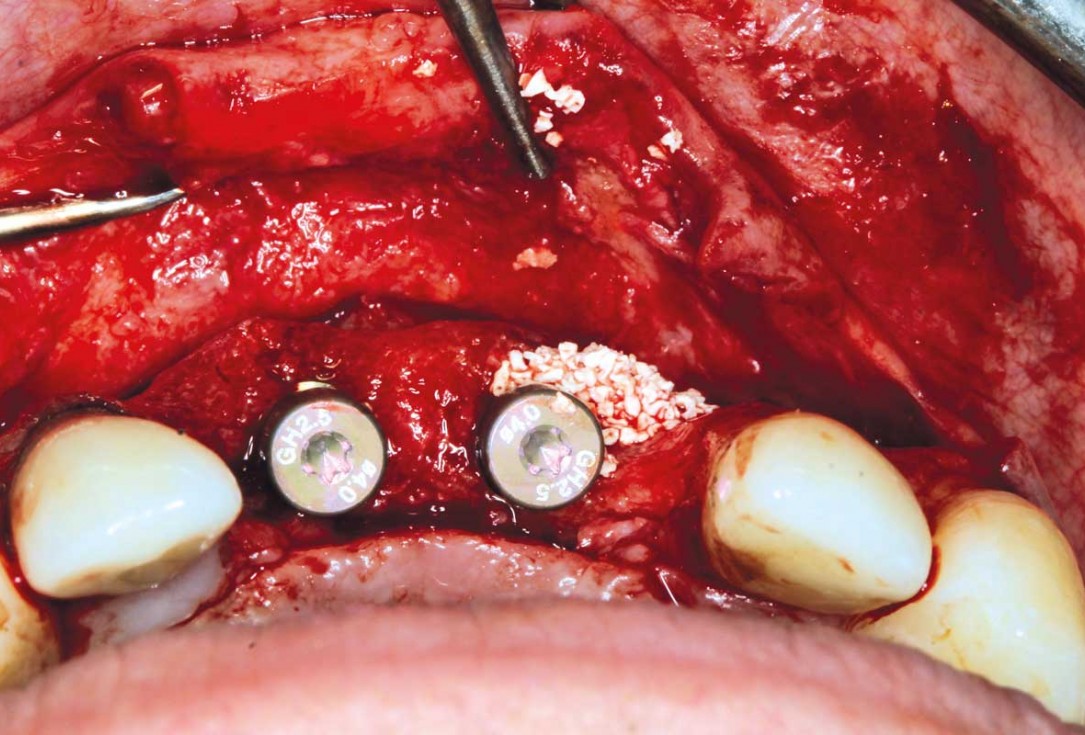

14/26 - Insertion of two Straumann BLX implants 3.75 x 14 mm / 3.75 x 12 mm

Ridge augmentation in the maxilla with maxgraft® bonebuilder in the aesthetic zone - Dr. M. Kristensen

17/26 - Insertion of two Straumann BLX implants 3.75 x 14 mm / 3.75 x 12 mm

18/26 - Insertion of two Straumann BLX implants 3.75 x 14 mm / 3.75 x 12 mm

19/26 - Contouring with cerabone®